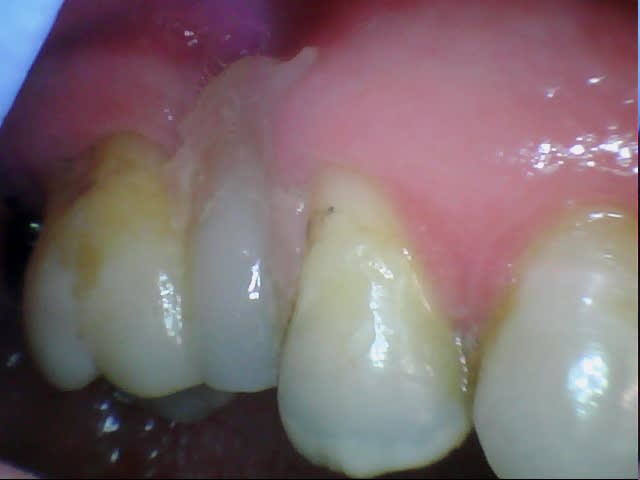

Easy : un p'tit netoyage des dents du bas paskessassevoi

CC.

Ah ... il y a des dents , 2 crochets .